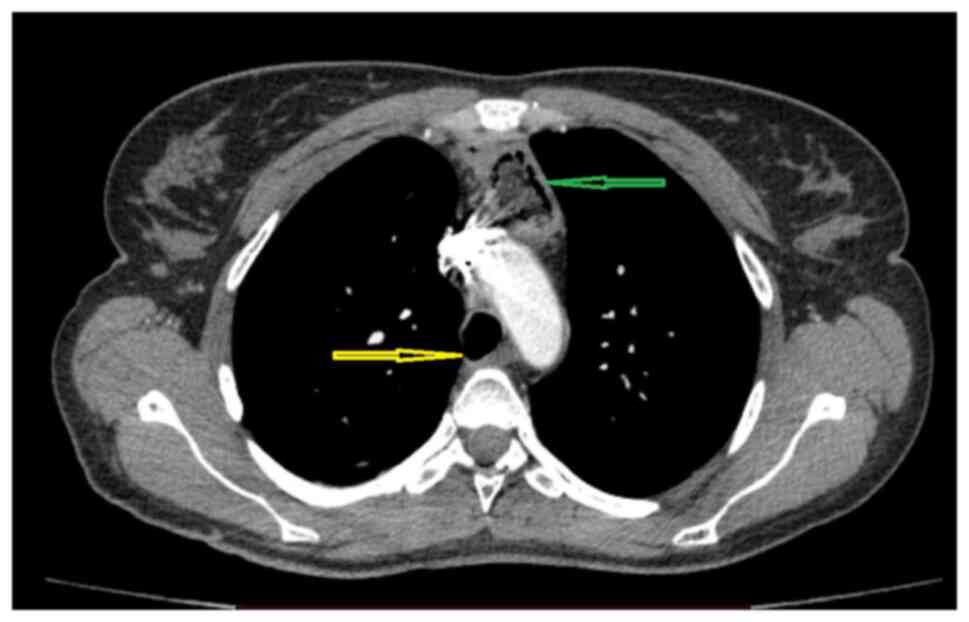

Acquired benign trachea‑oesophageal fistula is a rare benign pathological entity with varying aetiologies that most often occurs post‑intubation. This case report presents the case of a female patient, 31 years old, admitted to the emergency room with sepsis syndrome following bilateral aspiration pneumonia caused by a large trachea‑oesophageal fistula. The fistula was the result of intra‑tracheal migration of an oesophageal stent placed for post lye ingestion stenosis. Esophageal diversion and partial resection with oesophageal patch to repair the tracheal defect, under general anaesthesia with ventilation using rigid bronchoscopy and high frequency jet ventilation (HFJV), followed at a later date by esophageal replacement with colic graft were the procedures performed with a view to curing the patient. In conclusion, complex cases always require a tailored approach. It is important to note that HFJV may be applied for a longer period of time and the oesophagus can be used as patch for the posterior tracheal wall in selected cases. Staged surgery is also an option when the patients' poor health status does not permit major surgery.

Figure 1